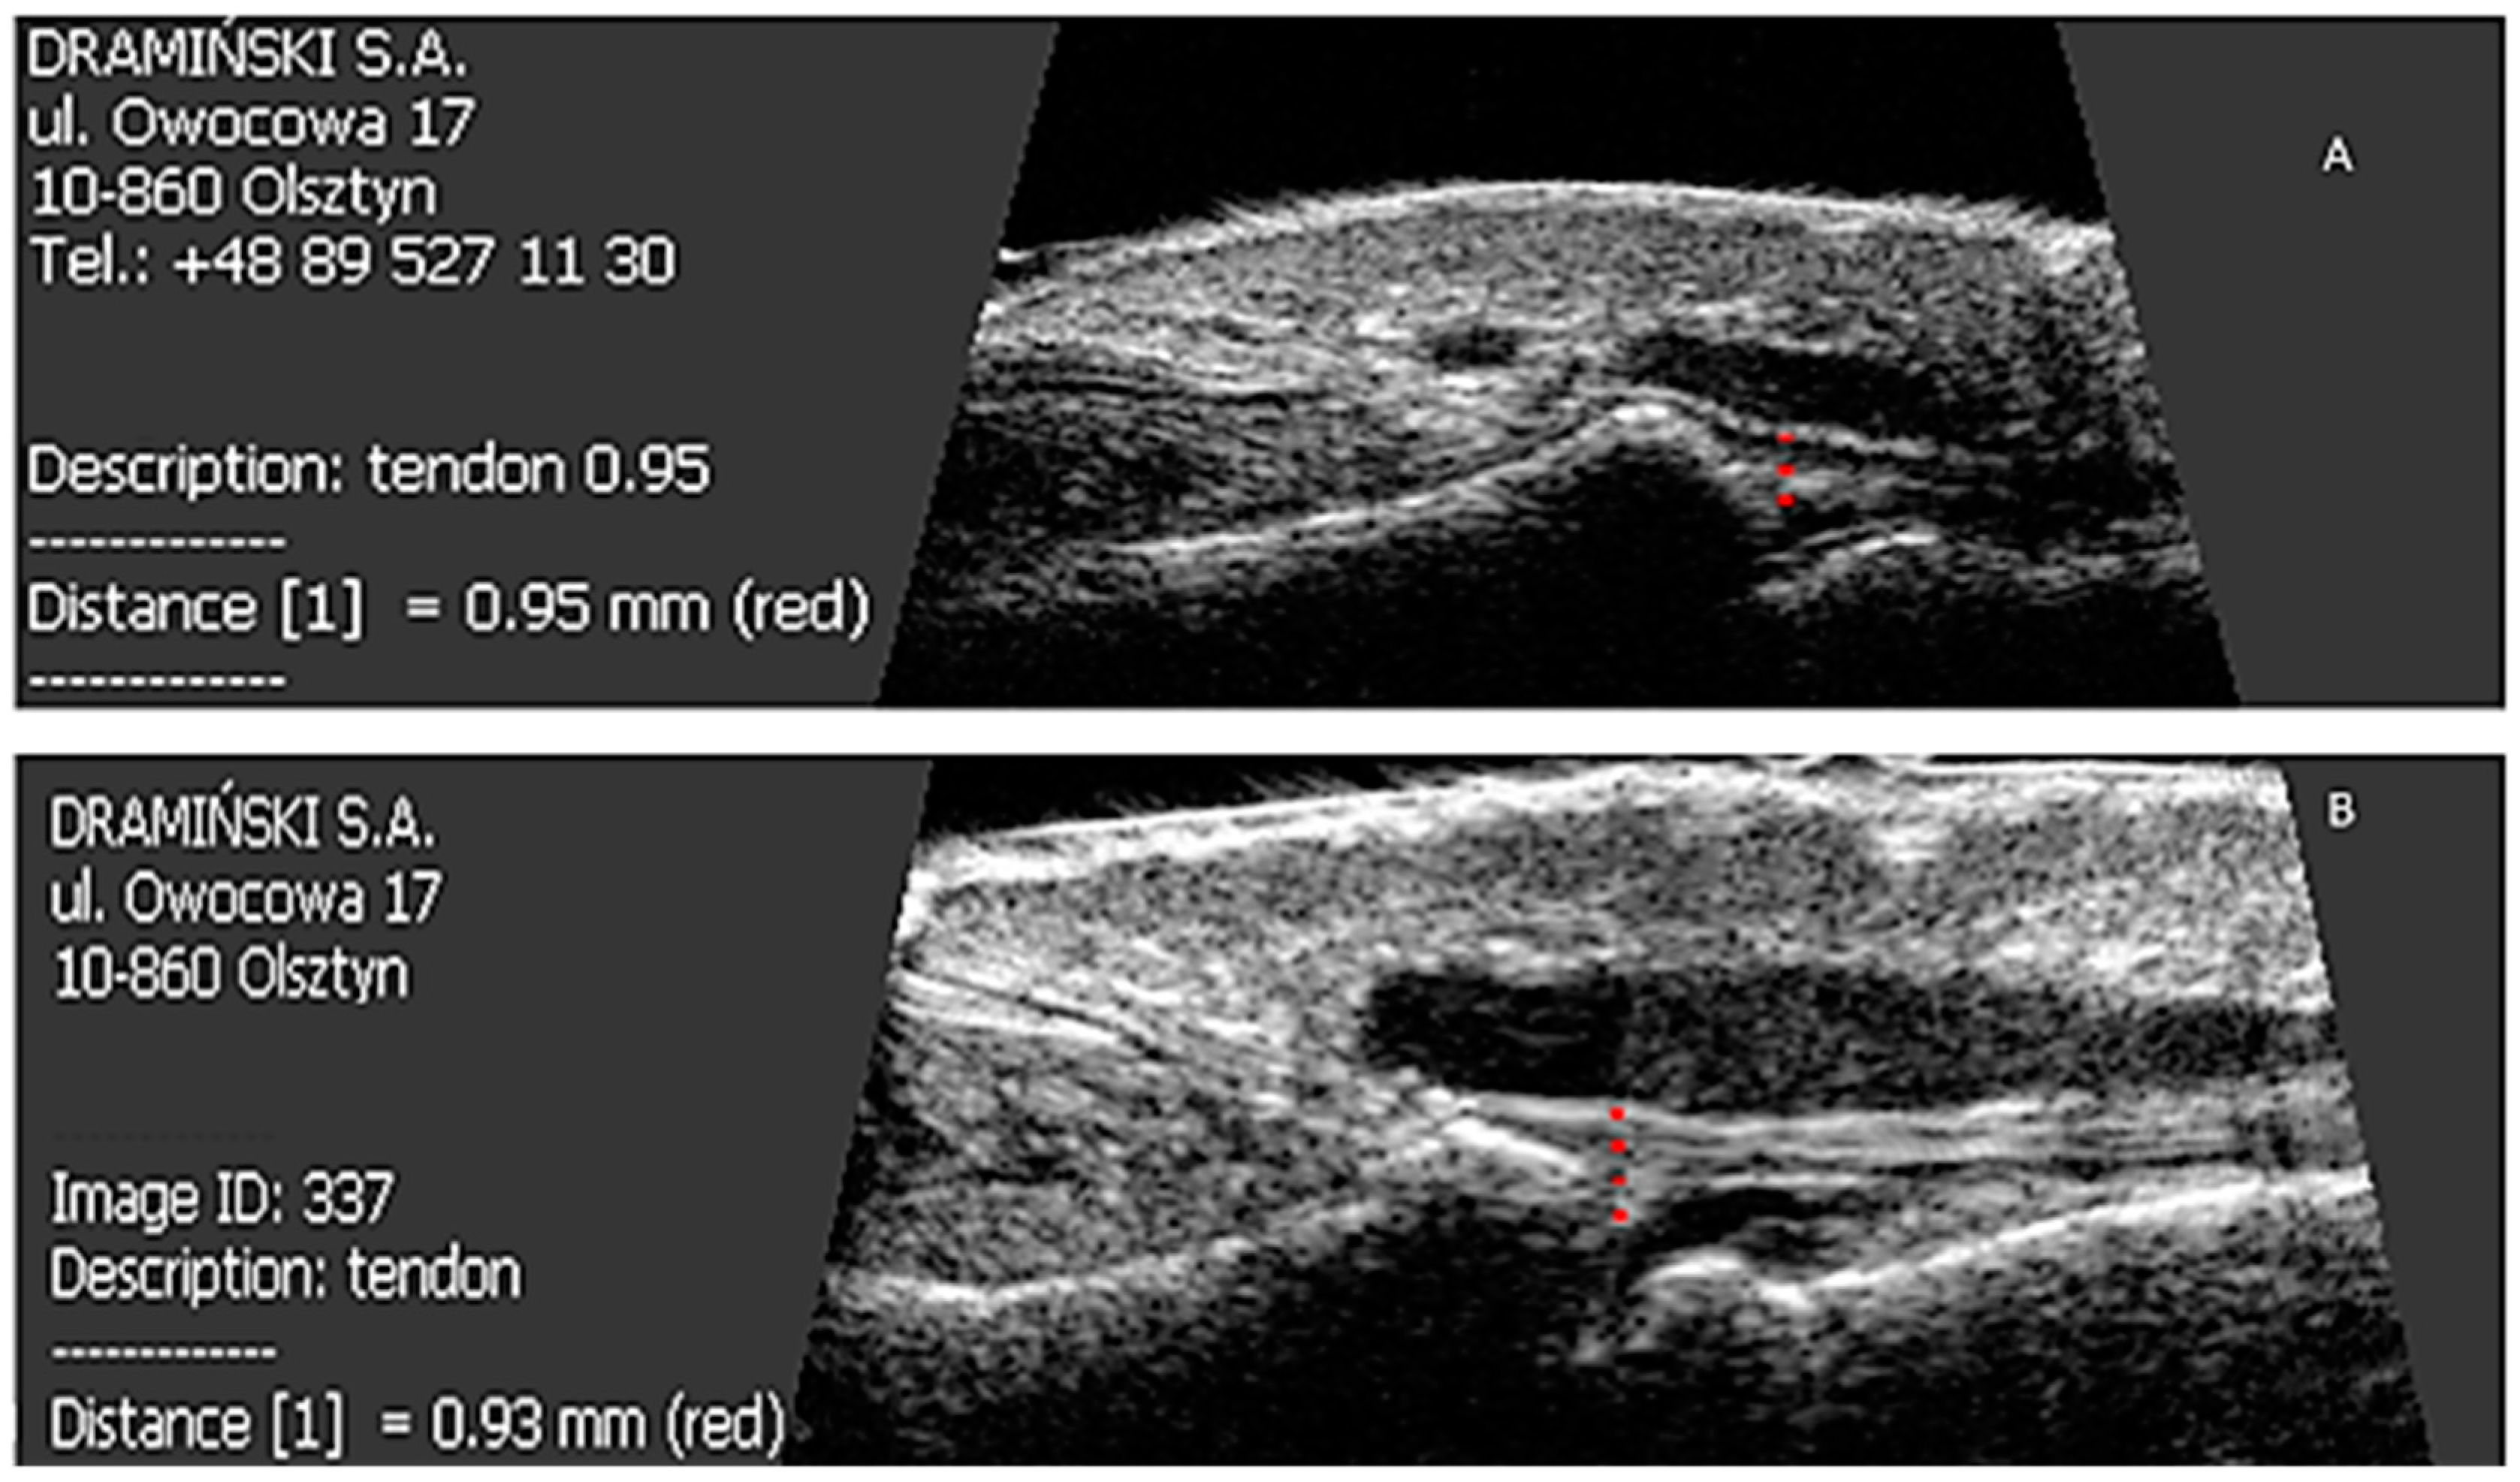

A total of 319 nails were examined: 190 nails in patients with psoriasis without arthritis and 129 nails in patients with PsA. Psoriatic changes in patients with Ps and PsA were present in 145 (76%) and 96 (74%) nails, respectively. Both the extensor tendon (Figure 1) and nail bed (Figure 2) in patients with PsA were thicker than in patients with psoriasis without arthritis (in both cases p < 0.001) and no statistical differences were observed in the thickness of nail plates and nail matrix. The nails with psoriatic changes were assessed in a US examination in regard to their morphology, in accordance with the classification proposed by Wortsman et al. (Figure S2). Focal hyperechoic involvement of the ventral plate (type I), loosening of the borders of the ventral plate (type II) and wavy plates (type III) in patients with psoriasis was observed in 83%, 11.5% and 5.5% of the nails under examination, respectively. No loss of definition of both plates (type IV) was observed. Type I, II, III and IV changes were present in 15.5%, 68%, 7% and 1.5% of the patients with PsA, respectively (Table 2). The digital extensor tendon was the thickest in type II of the changes in US in patients with Ps (p = 0.019), whereas no difference in the thickness of the extensor tendon was found in the group with arthritis depending on the type of changes of nail plates in an US examination. The thickness of the digital extensor tendon did not differ in patients with Ps and with PsA with the onycholysis and hyperkeratosis type changes (concomitant or existing separately), but it was significantly greater than in the pitting-type of changes (p = 0.041 and p = 0.033, respectively). A correlation was found in patients with Ps and PsA between the intensity of clinical changes in nails, as assessed with mNAPSI, with the thickness of the extensor tendon (r = 0.299, p = 0.042 vs. r = 0.336, p = 0.019, respectively). The tendon thickness in patients with Ps correlated with the matrix thickness (r = 0.346, p = 0.023) and the nail bed thickness (r = 0.285, p = 0.034), whereas in patients with PsA, the tendon thickness correlated with the nail bed thickness (r = 0.401, p = 0.011). No relationship between the thickness of the digital extensor tendon in a DIP joint with the intensity of skin changes was observed in either of the groups.

Figure 1. US measurements of tendon thickness in patients studied before and after methotrexate therapy. p < 0.001 Ps before therapy vs. PsA before therapy. p < 0.001 Ps before treatment vs. Ps after six-month therapy. p = 0.61 PsA before therapy vs. PsA after six-month therapy. Ps: psoriasis, PsA: psoriatic arthritis.

All patients were started on methotrexate after the first US examination. After six months of treatment, a decrease in the thickness of nail plates, nail beds and nail matrix was observed in both study groups (Table 4 and Table 5, Figure 3). Methotrexate treatment in the group of patients without arthritis reduced the extensor tendon thickness (Table 4, Figure 1), whereas no such effect was observed in patients with PsA (Table 5, Figure 1 and Figure 4). Methotrexate treatment in both groups reduced the intensity of vascularization as assessed with PD at entheses under study. An intensified PD signal in Ps patients after treatment was observed in 42/190 (22%) nails, like in the PsA group, where it was 29/129 (22.5%) nails.